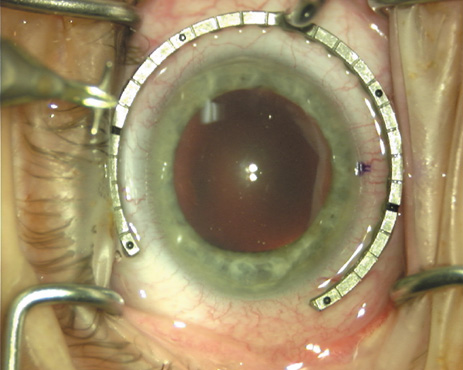

Case 2 is a 79-year-old woman who presented with a very dense left cataract. Her refraction was recorded at −2.25 +2.75 × 125 with a difficult end point. Her manual keratometry and topography measurements were consistent and revealed slightly less than 1.75 D at 120 degrees. Because of the questionable refraction, greater value was placed on the corneal measurements. Based upon the cataract nomogram, the plan was for paired LRIs of 40 degrees to be placed over the steep 120-degree axis (Figs. 1219).

Fig. 12. In this left eye, the steep meridian is at the 120-degree axis and has been delineated by opposing limbal marks. The upper left hand ink mark represents the 6:00 position for orientation. (Reprinted from Hardten DR, Lindstrom RL, Davis EA. Phakic Intraocular Lenses: Principles and Practice. Thorofare, NJ: SLACK Incorporated, 2004, with permission.)

Fig. 13. The incision is begun 20-degrees to one side of the centering mark. (Reprinted from Hardten DR, Lindstrom RL, Davis EA. Phakic Intraocular Lenses: Principles and Practice. Thorofare, NJ: SLACK Incorporated, 2004, with permission.)

Fig. 14. The incision is completed. (Reprinted from Hardten DR, Lindstrom RL, Davis EA. Phakic Intraocular Lenses: Principles and Practice. Thorofare, NJ: SLACK Incorporated, 2004, with permission.)

Fig. 15. Total arc length equals 40 degrees. (Reprinted from Hardten DR, Lindstrom RL, Davis EA. Phakic Intraocular Lenses: Principles and Practice. Thorofare, NJ: SLACK Incorporated, 2004, with permission.)

Fig. 16. The starting point of the opposing incision is determined. (Reprinted from Hardten DR, Lindstrom RL, Davis EA. Phakic Intraocular Lenses: Principles and Practice. Thorofare, NJ: SLACK Incorporated, 2004, with permission.)

Fig. 17. The opposing incision is begun. (Reprinted from Hardten DR, Lindstrom RL, Davis EA. Phakic Intraocular Lenses: Principles and Practice. Thorofare, NJ: SLACK Incorporated, 2004, with permission.)

Fig. 18. The incision is completed. (Reprinted from Hardten DR, Lindstrom RL, Davis EA. Phakic Intraocular Lenses: Principles and Practice. Thorofare, NJ: SLACK Incorporated, 2004, with permission.)

Fig. 19. The temporal single-plane clear corneal incision is placed independent of the LRIs. (Reprinted from Hardten DR, Lindstrom RL, Davis EA. Phakic Intraocular Lenses: Principles and Practice. Thorofare, NJ: SLACK Incorporated, 2004, with permission.)